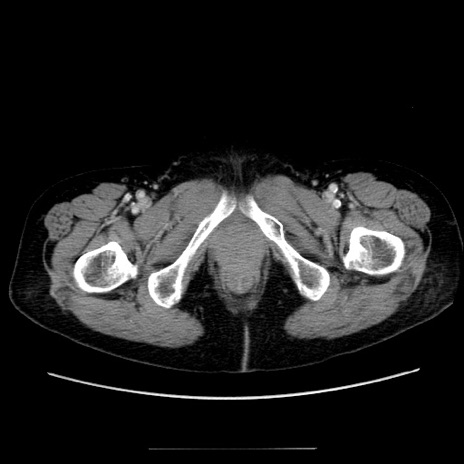

【症例】70歳代女性

【主訴】お腹が張る

【現病歴】1週間くらい前から腹部膨満の自覚あり。昨日夜から増悪したため、本日救急外来受診。

【身体所見】意識清明、BT 36.5℃、BP 165/106mmHg、HR 80bpm、SpO2 98%、腹部:膨満、軟、自発痛・圧痛なし、触診にて不快感あり、腸蠕動音:減弱

【データ】WBC 12600、CRP 1.04